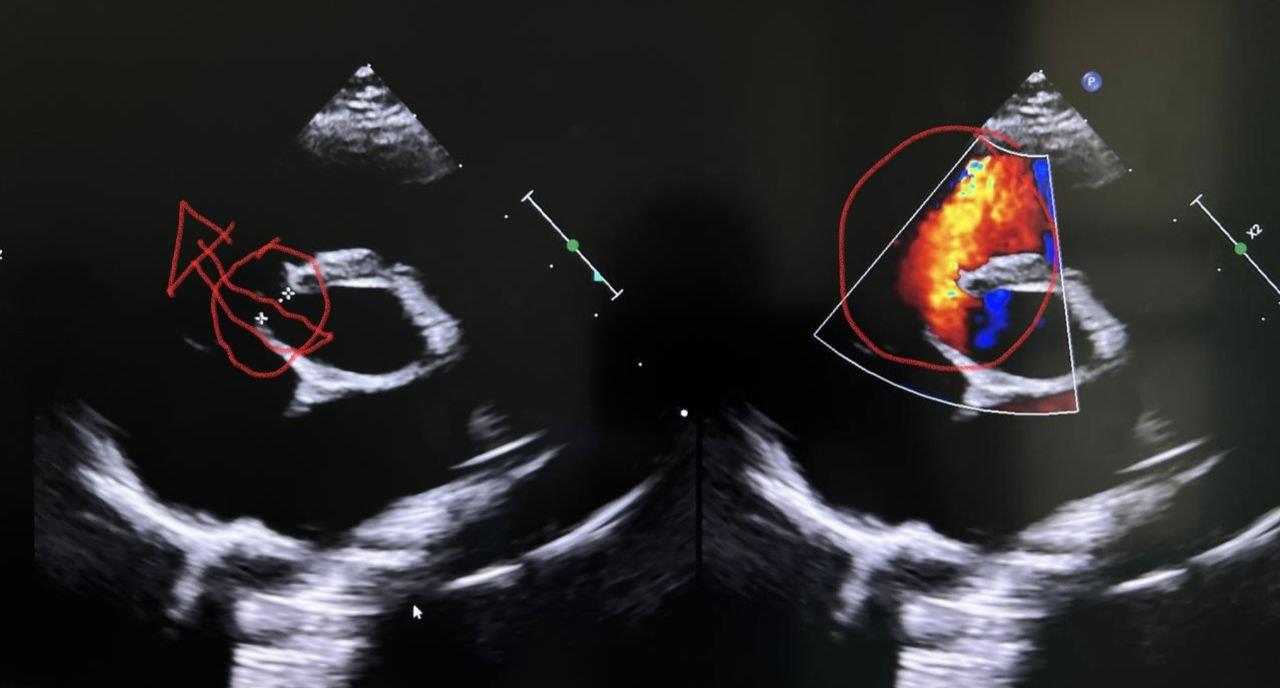

លោកស្រី យក់ សម្បត្តិ បានឱ្យដឹងទៀតថា បន្ទាប់ពីយកមកដល់មន្ទីរពេទ្យគន្ធបុប្ផា ក្រុមគ្រូពេទ្យបានរកឃើញថា កុមារី ធីដាណា មានបេះដូងចំហរថតក្រោមទំហំប្រមាណ៥មិល្លីម៉ែត្រ មិនទាន់បិទជិតនៅឡើយ ហើយទាមទារការវះកាត់បេះដូងដើម្បីភ្ជិតប្រហោងនោះ។

បន្ទាប់ពីក្រុមវេជ្ជបណ្ឌិតឯកទេសផ្នែកសង្គ្រោះ និងវះកាត់ផ្នែកបេះដូង នៃមន្ទីរពេទ្យគន្ធបុប្ផា បានពិនិត្យវាយតម្លៃស្ថានភាពទូទៅរបស់កុមារីរួចហើយនោះ

នៅរសៀលថ្ងៃចន្ទ ទី៣ ខែកក្កដា ឆ្នាំ២០២៣នេះ កុមារី ម៉ង់ ធីដាណា បានទទួលការវះកាត់។

លោកស្រី យក់ សម្បត្តិ បានឱ្យដឹងថា ក្រុមវេជ្ជបណ្ឌិតឯកទេសអស់រយ:ពេលប្រមាណ៤ម៉ោង។ ការវះកាត់ទទួលបានលទ្ធផលល្អជាជំហានដំបូង ដោយក្រុមគ្រូពេទ្យឯកទេសបានភ្ជិតប្រហោងបេះដូងដោយជោគជ័យ។ ក្រោយវះកាត់កុមារីរូបនេះ កំពុងស្ថិតនៅក្នុងបន្ទប់សង្គ្រោះក្រោយវះកាត់ និងសង្ឃឹមថានឹងដឹងខ្លួននៅព្រឹកថ្ងៃទី៤ ខែកក្តដា។